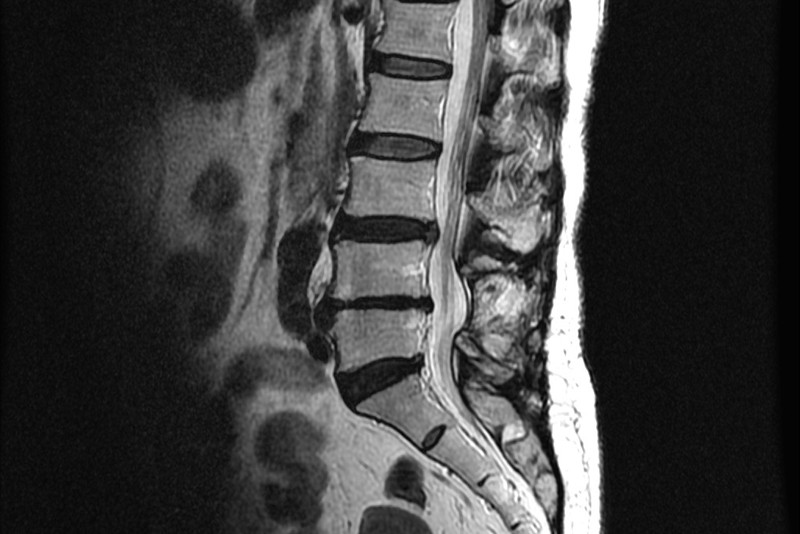

이번 포스팅에서 허리디스크에 좋은 운동 10가지에 대하여서 알아볼꺼에요. 허리는 우리 몸무게의 약 60%를 지탱하고 있습니다. 상당히 귀중한 육체 부위에요.

사무실이나 집에서 컴퓨터나 노트북을 하는 직장인들이 많다고 해서지면서 허리디스크 통증을 호소하는

분들이 불어나고 있다고 합니다.

허리디스크에 대해 아직 살펴보지 못하셨다면 허리디스크가 어느 부위를 말하는지 확인하시고 시기에 맞추어 운동하여 주십시요.